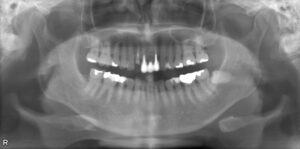

BEFORE AFTER 72歳男性/上顎1本欠損/インプラント埋込手術 【治療内容】 上顎前歯の被せものが取れてしまい…